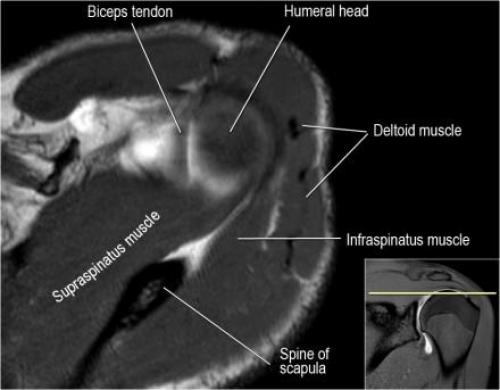

Хилл-Сакса мрт. Нормальная анатомия плечевого сустава в аксиальных изображениях и контрольный список.

- волокна сухожилия подлопаточной мышцы, создавая бицепитальную борозду, удерживают сухожилие длинной головки двуглавой мышцы. Изучите хрящи.

- уровень средней плече-лопаточной связки и передних отделов суставной губы. Поищите комплекс Буффорда. Изучите хрящи.